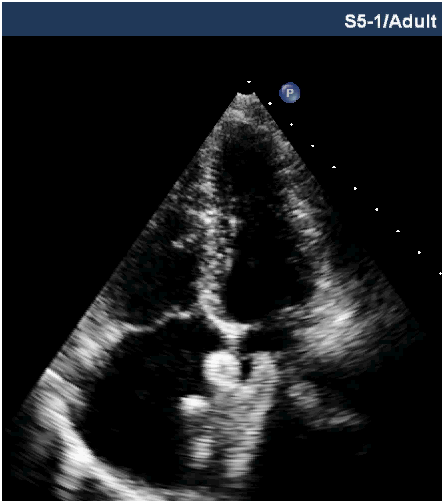

The patients were divided into two groups depending on echocardiographic guidance during device deployment. In group A TTE while in group B TEE was used as guiding tool for device deployment during percutaneous closure of secundum ASD. All patients were called a day before the procedure and clinical examination with complete blood count and chest X-Ray was done to rule out infection. An approval from ethical committee of the institution as well as written consent was taken before the procedure. The procedure was carried out with local or general anaesthesia. The device was deployed in a standard fashion under fluoroscopic and echocardiographic guidance. In some patients additional techniques including balloon assistance, dialator support or pull through were required for device deployment. The device position and residual leak was confirmed with TTE or TEE before the release of device (Figure 1 & 2). All patients were given I/V heparin 100u/kg and first dose of antibiotics (ceftriaxone) 50mg/kg during the procedure followed by two additional doses. The patients were discharged after 24 hours and TTE was performed at the time of discharge. The patients were advised aspirin 5mg/kg for six months and regular follow ups at 1,3 & 6months.

Figure 2 Transthoracic echocardiography showing well placed device.